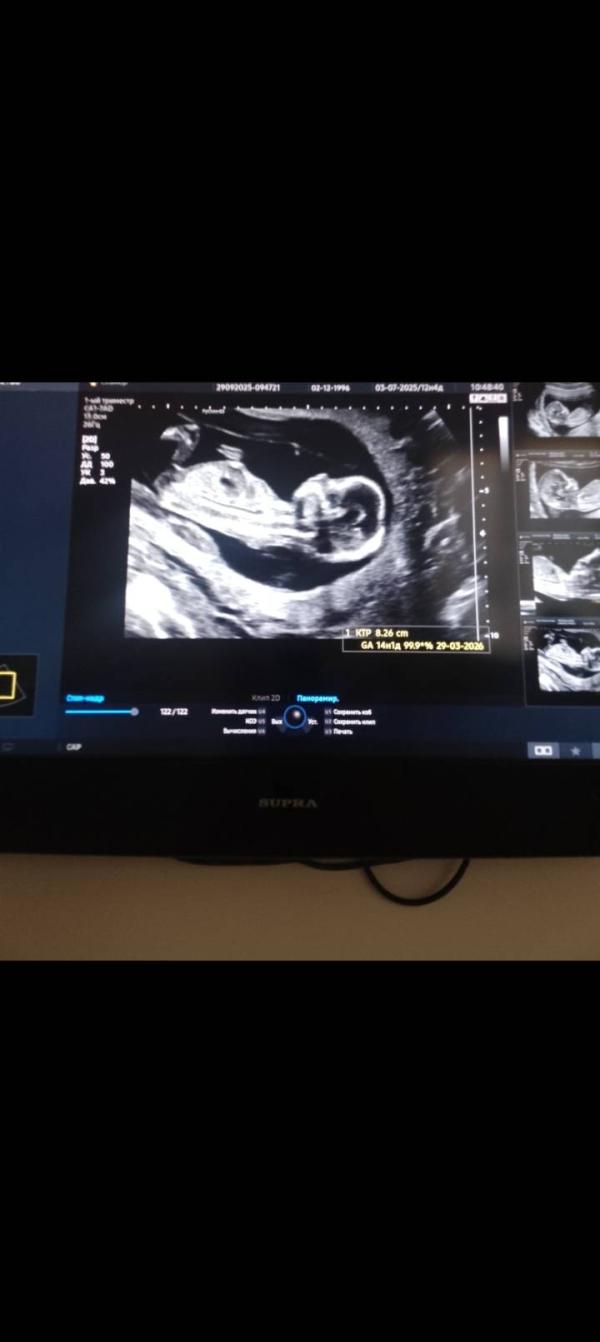

1 скрининг прошла ✅ 29.09.

По узи КТР 8.26 см, ЧСС 155. Плацента по передней стенке , тонус по задней стенке.

Срок 14 недель 1 день , ПДР на 29 марта🌹

Это я просто с экрана сама сфоткала)